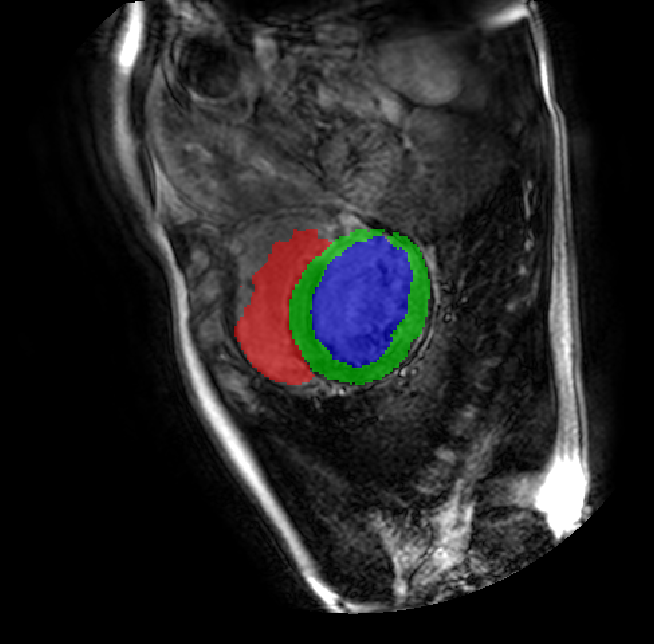

Table 2 presents an ablation study and compares SparseMamba-PCL with nine SOTA scribble-supervised methods across the three datasets. Out method achieves the highest Dice score across all the datasets, and the lowest (CHAOS) and second lowest (ACDC and MSCMRSeg) HD95 values, confirming its effectiveness in segmentation accuracy and boundary refinement. Baseline+SPOBE and Baseline+PCL improve upon the Baseline (SparseMamba), demonstrating the benefits of boundary-aware supervision and SAM-guided learning. Fig. 4 (l) compares the segmentation performance of SparseMamba-PCL with other scribble-supervised methods, showing smoother edges that precisely delineate object boundaries, unlike the jagged or blurred edges in other methods. The examples also demonstrate the consistent segmentation quality achieved by SparseMamba-PCL across ACDC, CHAOS, and MSCMRSeg, highlighting its adaptability across multiple medical domains. This adaptability and precise segmentation is crucial for accurate volumetric analysis and clinical decision-making, where even subtle boundary inaccuracies can lead to diagnostic errors. In summary, the SparseMamba-PCL architecture provides a consistent and robust improvement in segmentation metrics across diverse medical image datasets.

Refer to caption Refer to caption Refer to caption Refer to caption Refer to caption Refer to caption Refer to caption Refer to caption Refer to caption Refer to caption Refer to caption Refer to caption

(a) (b) (c) (d) (e) (f) (g) (h) (i) (j) (k) (l)

Figure 4: Qualitative comparison of weakly-supervised segmentation methods on ACDC, CHAOS, and MSCMRSeg datasets. (a) Input image, (b) ground truth, and segmentation results from (c) USTM [16], (d) Scribble2D5 [5], (e) CycleMix [26], (f) ShapePU [27], (g) S²ME [21], (h) ScribbleVC [12], (i) TDNet [30], (j) PacingPseudo [25], (k) Scribbleformer [13], and (l) SparseMamba-PCL are given.